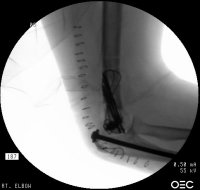

Click for larger image

Finally, the titanium olecranon screw was replaced with a longer 6.5 mm stainless screw and tension band wire. Following this, the elbow was stabilized with an EBI hinged external fixator (not shown), planning to leave this on four weeks, anticipating inadvertent weight bearing due to the patient's bilateral calcaneal fractures.